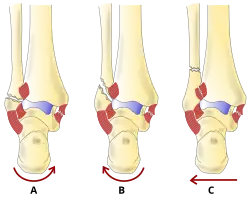

Gegenwärtig werden die Brüche für die operative Versorgung bevorzugt anatomisch nach Danis oder abgeleitet nach Weber[2] eingeteilt, und zwar abhängig von der Höhe des Wadenbeinbruchs im Verhältnis zur bindegewebigen Verbindung zwischen Waden- und Schienbein (Syndesmose). Diese Einteilung wurde von der Arbeitsgemeinschaft für Osteosynthesefragen (AO) in ihre Klassifikation übernommen und weiter differenziert:

| Typ | Frakturlokalisation | Syndesmosenverletzung |

|---|---|---|

| A | Fraktur unterhalb der Syndesmose | Syndesmose immer intakt |

| B | Fraktur auf Höhe der Syndesmose | Syndesmose häufig mitverletzt |

| C | Fraktur oberhalb der Syndesmose | Syndesmose immer mitverletzt |

Das Ausmaß der Gelenkschädigung steigt von A bis C an. Begleitverletzungen wie Innenknöchelbruch und hinteres Schienbeinkantenfragment (Volkmann’sches Dreieck) können das Ausmaß der Gelenkschädigung erhöhen.

Diese Einteilung bezieht sich ausschließlich auf die örtliche Lage des Wadenbeinbruchs. Aus der Zuordnung lässt sich annähernd auf die zu erwartende begleitende Läsion der gabelstützenden Bänder der Syndesmosen-Region und der Membrana interossea schließen.